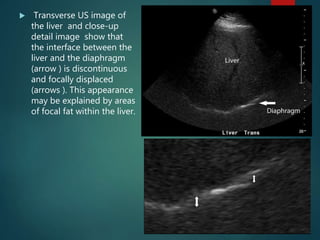

 Transverse US image of

the liver and close-up

detail image show that

the interface between the

liver and the diaphragm

(arrow ) is discontinuous

and focally displaced

(arrows ). This appearance

may be explained by areas

of focal fat within the liver.

 In this diagram, the gray arrows

represent the expected reflected path of

the ultrasound beam. The echoes

returning from the posterior wall of the

depicted structure will be displayed

properly. The black arrows represent the

path of an ultrasound beam that

encounters an area of focal fat. The

dashed lines indicate that the sound

beam travels slower in the focal fat than

in the surrounding tissue.

Because the round trip of this echo is longer than

expected, the posterior wall is displaced deeper

on the display.